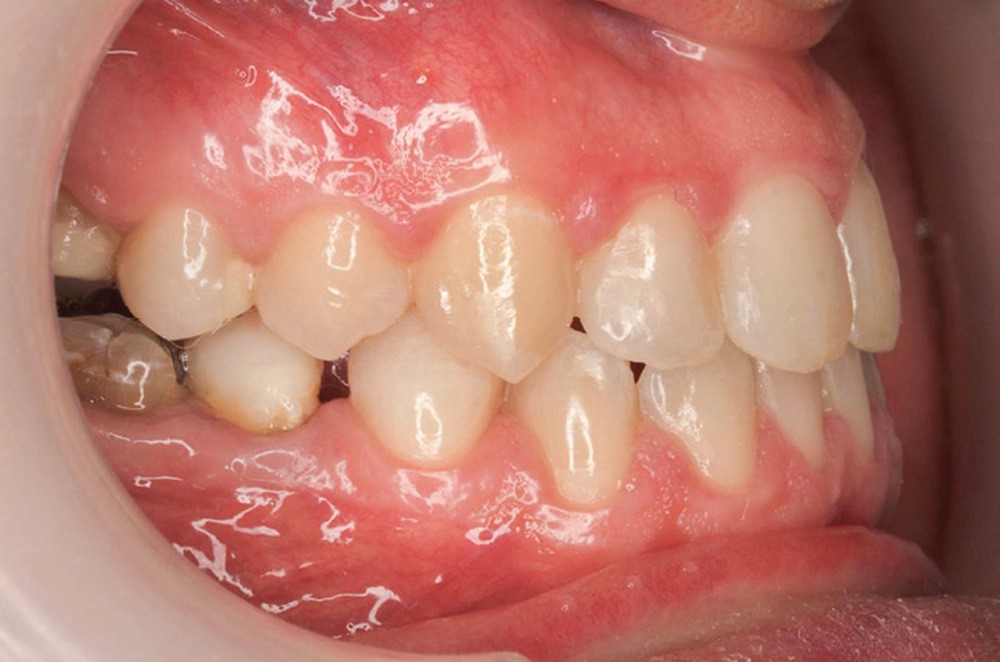

Diagnostic (fig. 1a-g)

La patiente présente une classe III squelettique dans un contexte hyperdivergent associée à une endoalvéolie maxillaire, un articulé inversé antérieur, une rétroversion incisive maxillaire, des rapports de classe I canine bilatérale, une absence de 16 et 36.

Au niveau esthétique, le profil est rectiligne. La lèvre supérieure est plus effacée, en retrait par rapport à la lèvre inférieure. De face et de profil, la mandibule paraît massive et le maxillaire effacé : le manque de soutien de la lèvre supérieure contribue à cette impression.

Le sourire est étroit, dégradé par les malpositions dentaires.

Au niveau fonctionnel, il existe un pro-glissement mandibulaire et un articulé inversé antérieur. Le profil téléradiographique montre en occlusion des rapports labiaux et un profil de classe III plus marqué que sur photographies.